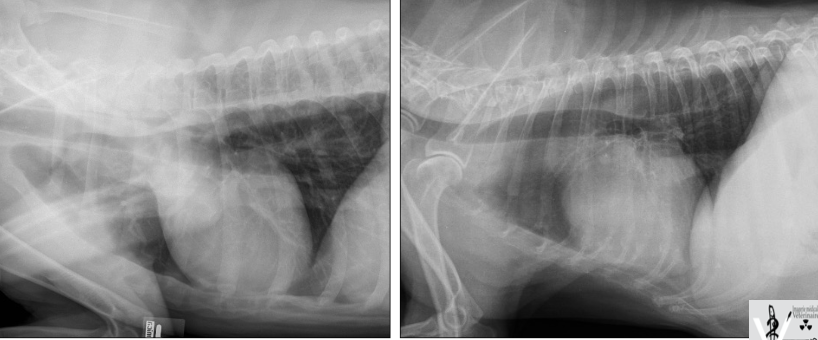

Critiquez l’exposition de cette radiographie.

A) elle est adéquate

B) elle est sous-exposée

C) elle est surexposée

D) l’appareil est défectueux

C)

Laquelle des 2 radiographies a été prise avec un filament de taille plus petite?

B : on y voit mieux les rebords osseux. Ici, c’est une partie du corps immobile et on peut se permettre d’augmenter le temps afin de diminuer le mA et donc le filament.

La taille du filament affecte le mA : plus petit = mA plus bas

À mAs équivalent : temps augm, mA diminue => permet d’avoir une meilleure netteté